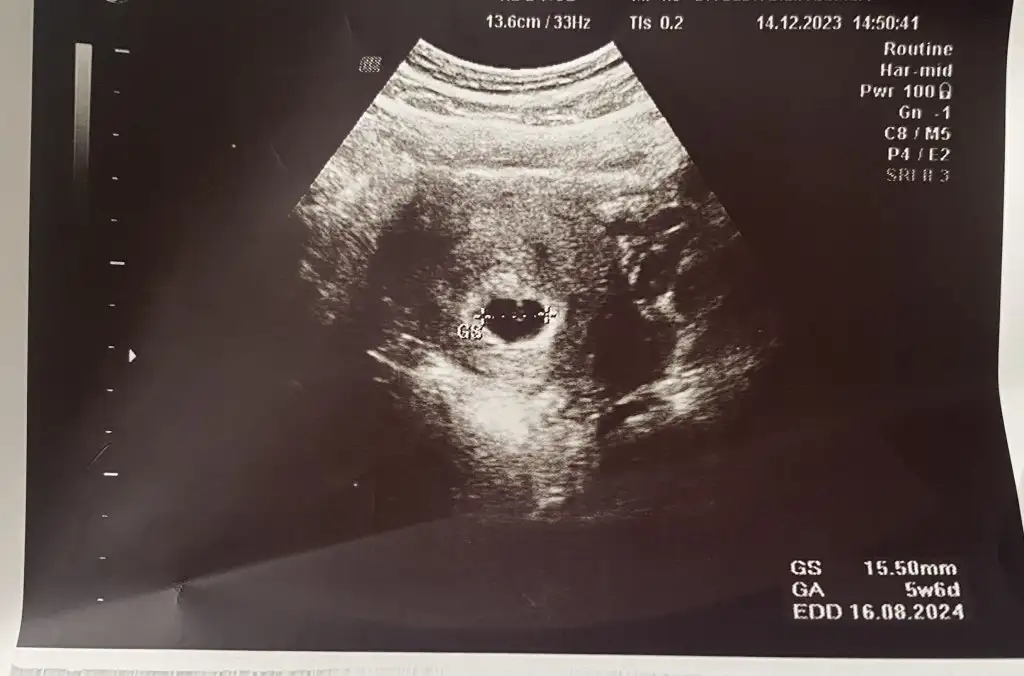

Tabi ki yaşınız ve şehir neresidir? kese göründüyse hangi hafta yazabilir misiniz? :)son adet tarihim 14.11.2023 tahmini doğum tarihi 20.08.2023 ikinci çoçuk benide eklermisiniz

Hayırlı olsunn :) dilerseniz bilgilerinizi yazın tabloya yazayım sizi de :)Selam kızlarbende bugün ilk kontrolüme gittim , kalp atışı ve bebeği görmek için henüz erken , 10 gün sonra gelin dedi . Kesenin ortasındaki beyazlık bebeği besleme kanalı dedi . Beyazlık kenarındaki küçük beyaz nokta da sanırım bebek , doktor böyle söylemedi ama Banu Çiftçi videosunda öyle söylüyordu ortada pırlanta yüzük görürsünüz , yüzük kısmı yolk kesesi , pırlanta kısmı bebek diye son adet tarihine göre 5+4 tü , ancak yumurtlamaya göre 5+6 dı . Cihazda yumurtlamaya uygun çıkardı sanırım .bolca süt ürünleri yememi söyledi yoğurt kefir gibi .

Hayırlı olsun.son adet tarihim 14.11.2023 tahmini doğum tarihi 20.08.2023 ikinci çoçuk benide eklermisiniz